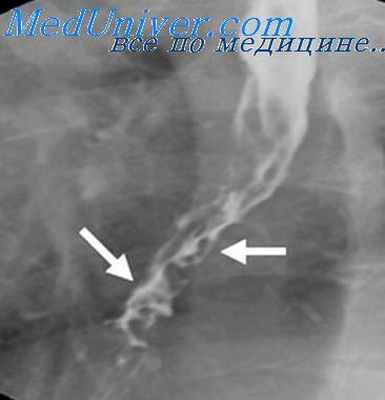

В выраженных случаях варикозного расширения вен пищевода на фоне несколько измененного рельефа слизистой оболочки, имеющего ячеистый или кружевной вид, выявляются множественные округлой или овальной формы дефекты наполнения. Варикозные узлы нередко располагаются цепочками по ходу вен в виде образований, напоминающих полипы, или в виде коротких извилистых разной величины прозрачных полосок. В тангенциальной проекции они формируют неравномерную, но достаточно четко очерченную зубчатость контуров пищевода.

В процесс раньше всего зовлекаются вены нижнего отрезка пищевода, поэтому они всегда изменены в большей степени, чем вены вышележащих отделов пищевода. Явное сужение просвета пищевода при этом отсутствует, эластичность и сократительная способность стенок не нарушаются. Размеры дефектов наполнения меняются при приеме густой бариевой взвеси, сдавливающей варикозные узлы, а также под влиянием функциональных проб, покашливания и перемены положения тела. При сокращении пищевода узлы могут исчезать, а при расслаблении — появляться вновь. Изображение же опухолевых узлов остается постоянным. Кроме того, для варикозного расширения вен характерны частые кровотечения, гипотония, зияние кардии, а также несоответствие между небольшими проявлениями дисфагического синдрома (неприятные ощущения лишь при проглатывании горячей пищи) и многочисленными рентгенологическими данными. Решающие для диагноза данные могут быть получены с помощью спленопортографии, когда контрастное вещество заполняет измененные сосуды пищевода и желудка [Карицкая Г. К., 1966; Кишковский А. Н., Дударев А. Л., 1971, 1972]. Однако потребность в этом исследовании с целью распознавания варикозного расширения вен пищевода возникает чрезвычайно редко.